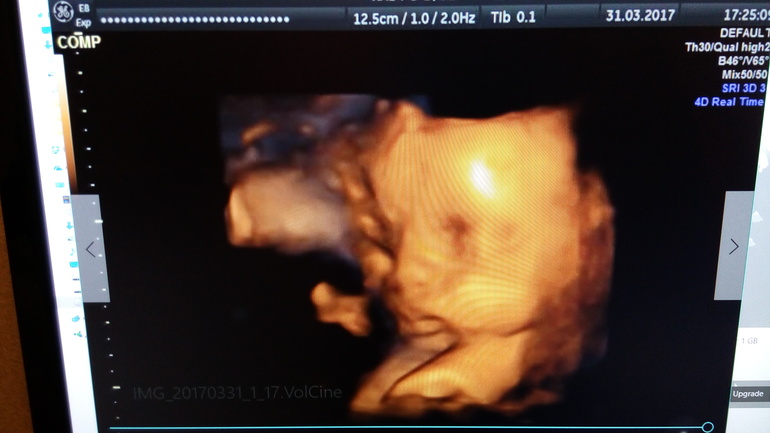

Наши 28.5 недель)

Сегодня съездили на УЗИ. Перед УЗИ съела сладкий пирожок и выпила капучино. Думала, что мелкий расшевелить счет от сладкого. Да не тут то было. Далее по кат.Наш малыш любитель поспать во время УЗИ) Вот и сегодня он в очередной раз доказал, что УЗИ нисколько не причиняет ему неудобств. Как ни пыталась его врач расшевелить, он сладко спал с полным желудком. Как настоящий мужчина - поел и на боковую. И ничто его не могло потревожить) Свернулся клубочком - коленками упирался в лоб. Так что четких фото в 3д, как я надеялась, не получилось. Но все же мы разглядели пухленькие щечки и не менее пухлые губки) . Весит уже 1500 кг примерно. Все соответствует сроку. А вот ноги и руки, как и в 16 недель , опережают по длине на неделю, полторы. Баскетболист там у нас похоже растет))) Руки на 30 недель, а ноги аж на 30.5! Похоже , опять вылитый муж.) Дочь у нас вылитый папа и лицом фигура ( ноги от ушей)))) Сынуля , видимо тоже))) Тонус мой чудесным образом исчез и миома тоже. Как ни старались, не нашли). Пока сидим на попе. Надеюсь, успеем перевернуться в головное.